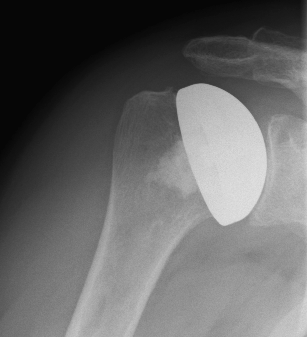

Abbildung3Abbildung4Surface replacement ("cap prosthesis" of the humeral head) in cases of mild omarthrosis and still well-preserved glenoid cavity

links: X-ray image of a cap prosthesis ("surface replacement")

right: cap prosthesis ("surface replacement", type "Durom" Fa. Zimmer)gkl